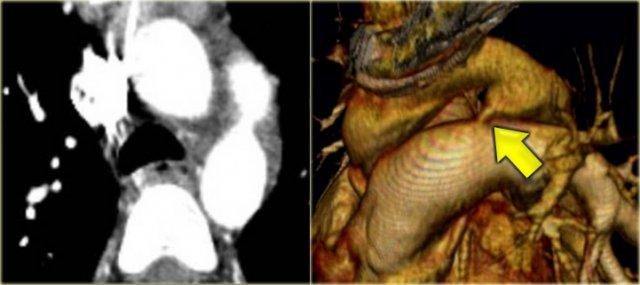

Double Arch with Atretic Segment

Occasionally the double arch can have an atretic segment.

You should not confuse it for a right arch.

The left arch is just very small and there is still a four vessel sign.

On the left a dominant right arch and a small left arch.

The atretic segment is marked by the arrow.

Notice the four vessel sign.

On a posterior view the interruption is nicely demonstrated.

Remember that there is still a ring, so there is still obstruction.

Another case on the left.

Do not call this a right arch.

It still is a double arch and there is a atretic fibrotic segment on the posterior side of the left arch, that completes the ring.

Same patient.

Always look at the airways.

On the recoonstruction the impression on the trachea is better appreciated.